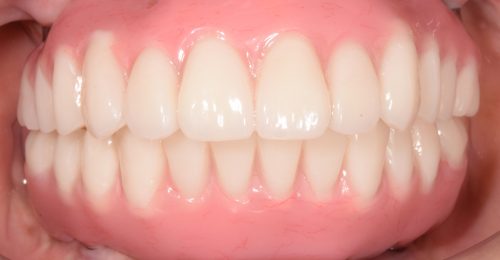

• オールオン4(上顎4本下顎4本)

術前

術後3年以上

年齢・性別 75歳・女性

治療期間 5ヶ月、通院回数18回

治療費用 5,492,080円(税込)

治療内容 1年前に作った入れ歯が痛くなり噛めない。バネも歯肉に刺さると来院。今回は入れ歯ではなくしっかり噛みたいということでオールオン4を希望。